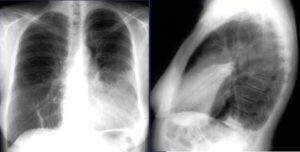

Вспышки пневмонии «любят» зимние и весенние месяцы. Пневмония не редкость, поэтому вы должны знать о ее первых признаках и симптомах. Почему-то большая часть граждан обращается к врачу, когда все симптомы пневмонии присутствуют в полной мере. Осложнений можно избежать, если провести грамотную самодиагностику. В этой статье мы разберемся, какие симптомы «сигнализируют» о возможной пневмонии. Первые признаки …

При диагностике пневмонии у детей, помимо клинического обследования и рентгенографии грудной клетки, проводятся различные виды тестов, от простых анализов крови до ПЦР-тестов для выявления конкретных патогенов. В следующей статье мы кратко рассмотрим методы диагностики и обсудим изменения общего анализа крови и COE, характерные для пневмонии. Виды исследований Родители хорошо знают своего ребенка и поэтому при …